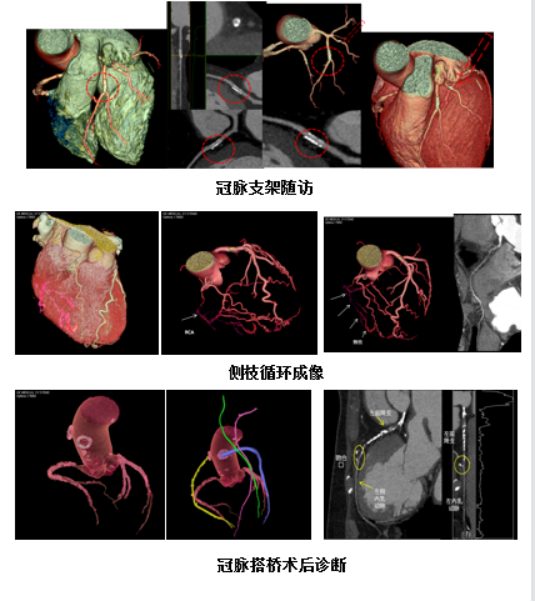

精準心臟檢查